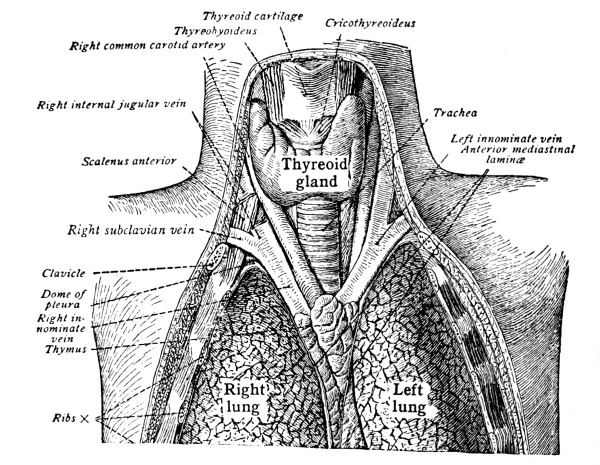

The Larynx, 121—The Trachea, 123—The Thyroid Gland, 124—The Thymus Gland, 124—The Bronchi, 125—The Lungs, 125—The Pleura, 125—The Mediastinum, 126—Respiration, 127—Air, 129—Respiratory Sounds, 129—Changes in Air in Lungs, 129—Effect of Respiration on Blood, 130—Nervous Mechanism of Respiration, 130—Variations in Respiration, 131. |